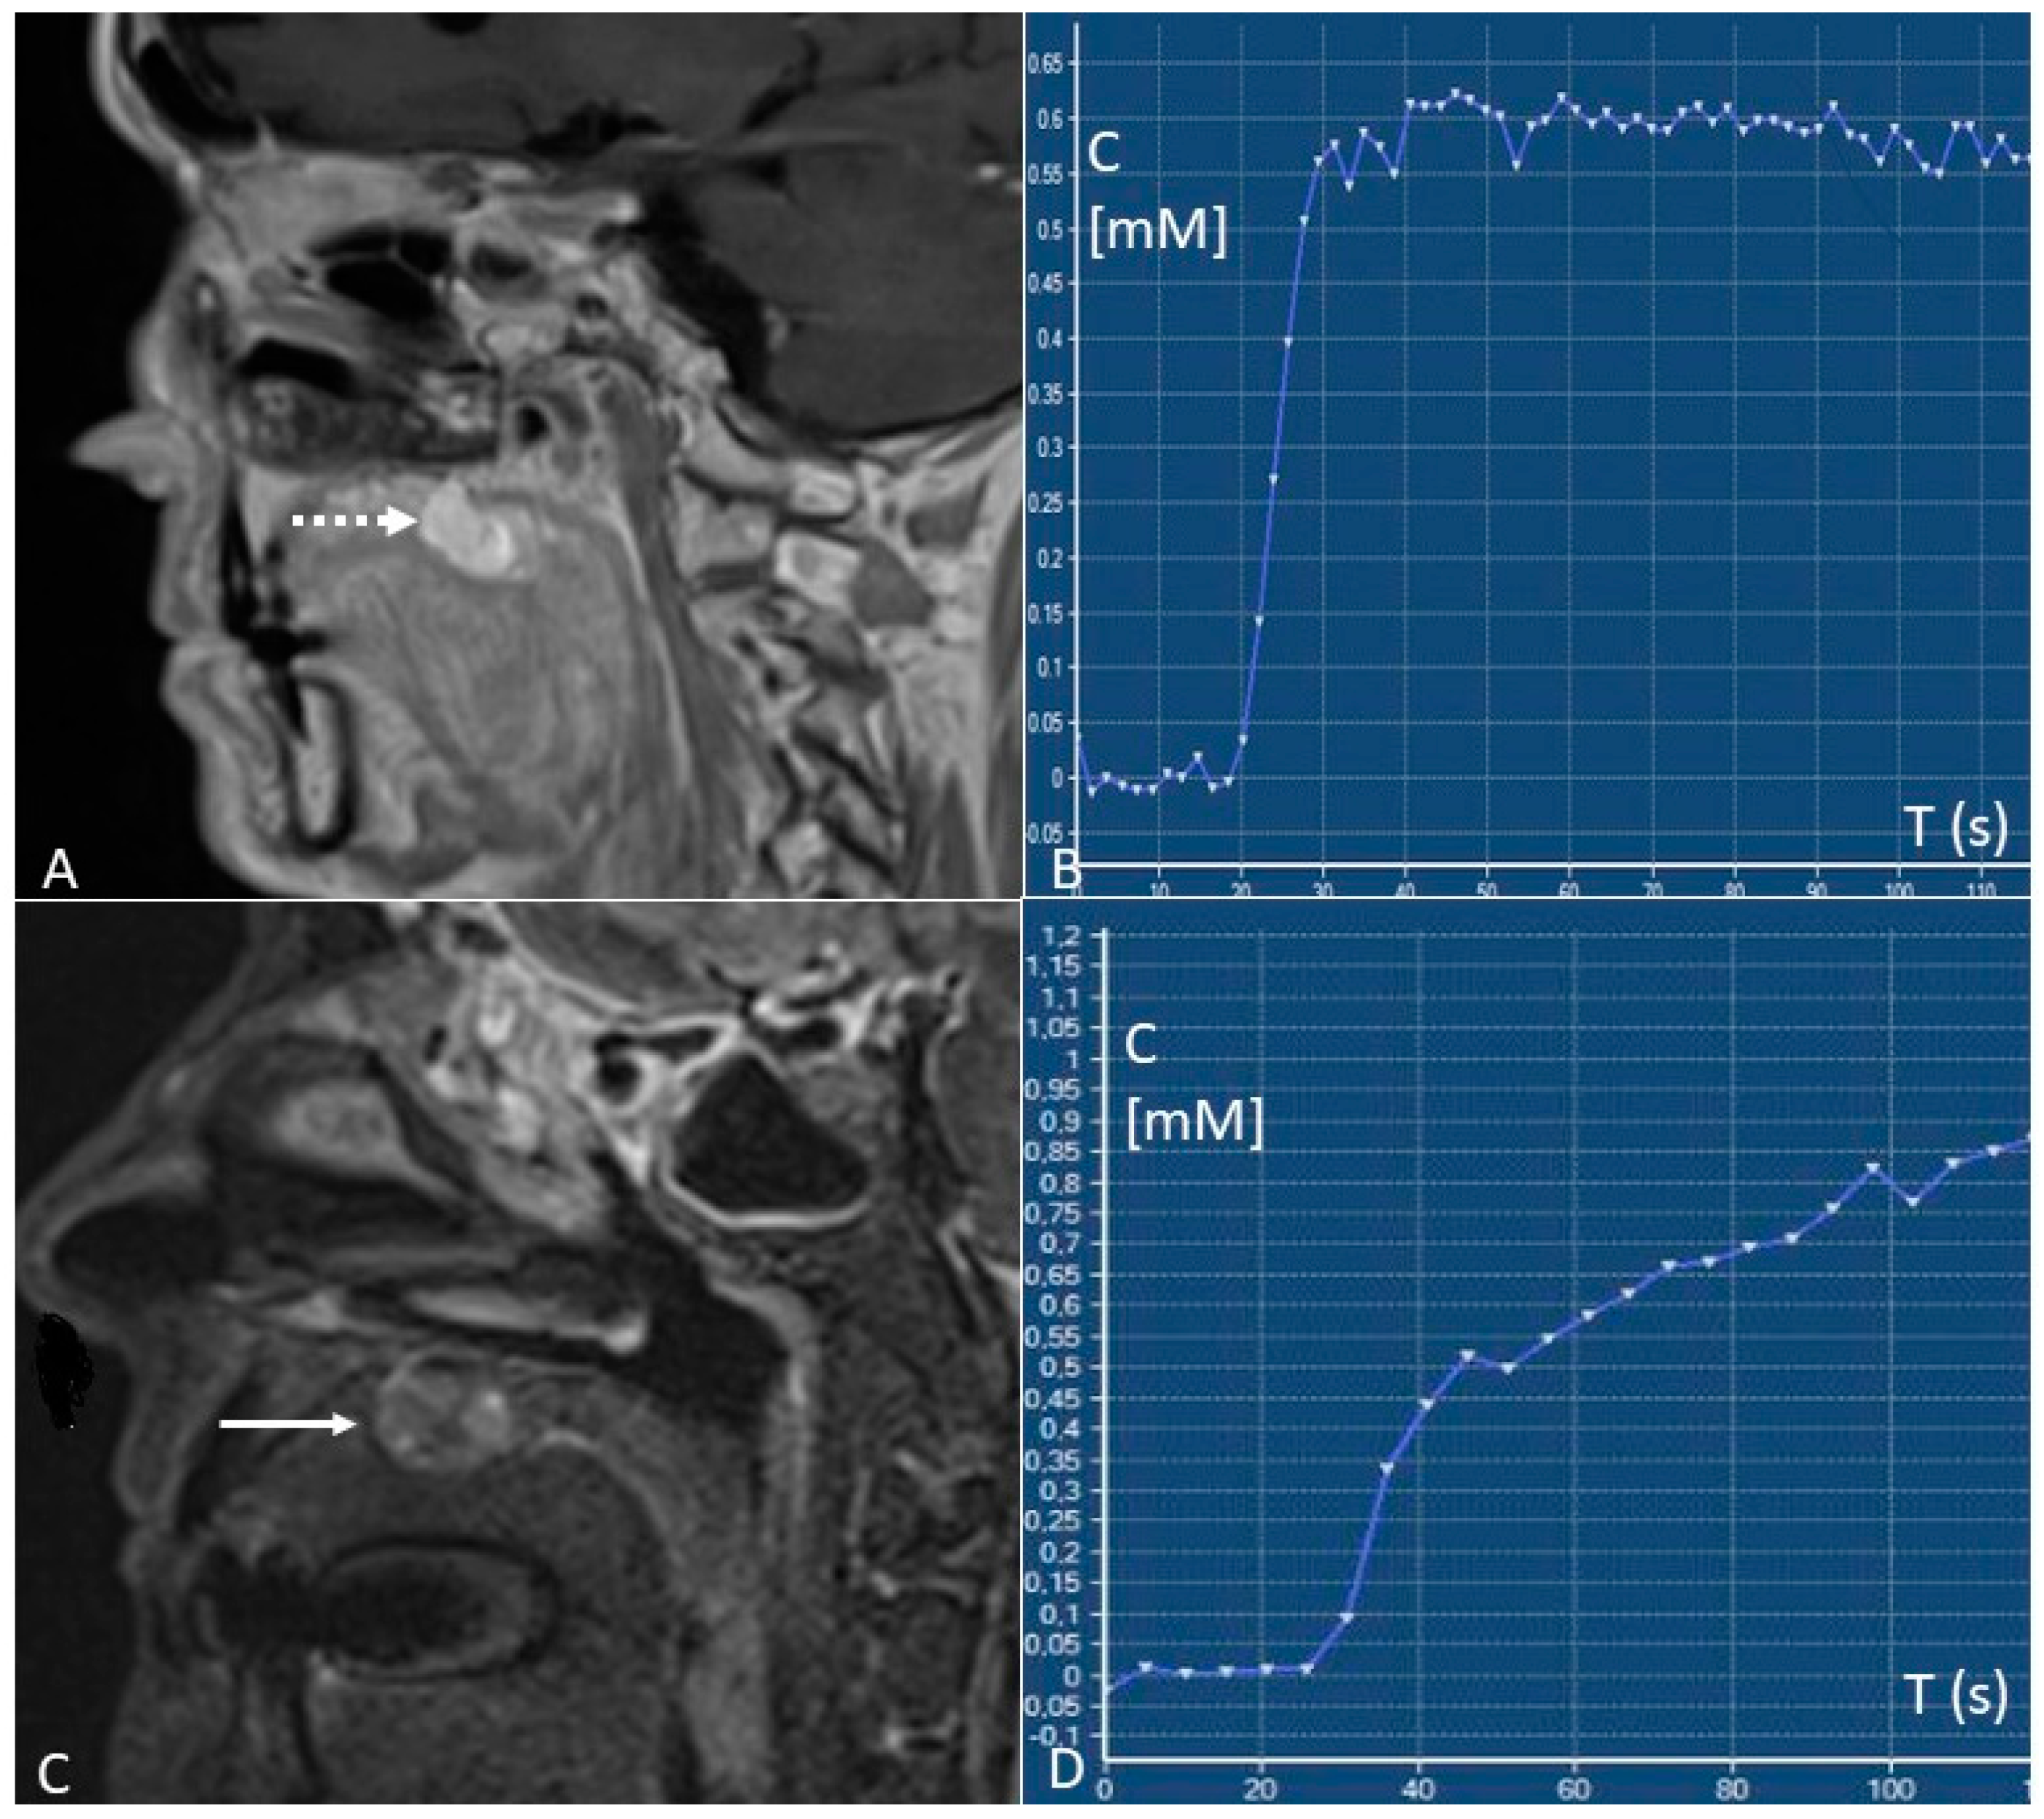

4.2.2. DCE–PWI

- Early identification of locoregional recurrences by the differentiation between local recurrences and post-treatment changes. Relapses show type B or C time/intensity curves (wash-in with wash-out or plateau), whereas post-treatment changes predominantly show type A curves (progressive enhancement). “Time factor” is crucial since a too-short interval of time from surgery or radiotherapy (<3–4 months) can determine false positives due to the presence of inflammatory areas and oedema with vivid enhancement [41];

- Predict pathological stages of oral cancer. For oral tongue squamous cell carcinomas, that are the most frequent malignancies of the oral cavity, staging before treatment is essential since a stage I-II TNM can be treated with a single modality therapy (preferably surgery), whereas stage III-IV TNM have to be treated with multi-modality therapy. Depending on the TNM stage, oral cavity cancers have a different microvasculature function reflected in different pharmacokinetic parameters at the quantitative DCE-MRI analysis. Stage I–II tumours show higher Ktrans values than stage III-IV tumours (0.149 ± 0.080 vs. 0.106 ± 0.057 min−1) [42];

- Differentiate metastatic from normal lymph nodes. Yan et al. [45] found that the value of Ktrans in nodal metastases from squamous cell carcinoma is higher than benign nodes (0.328 ± 0.111 vs. 0.141 ± 0.065 min−1);

- Predict tumour response to treatment. Although with a high metastatic potential, highly perfused tumours are considered to have a better therapeutic response because they receive a great amount of chemotherapy and are more sensitive to radiotherapy. The most accurate pre-therapy DCE-MRI parameter for predicting tumour treatment response is Ktrans. Higher pre-therapy Ktrans values are associated with a better response to therapy, with threshold values > 0.41 to 0.84 min−1 [46].